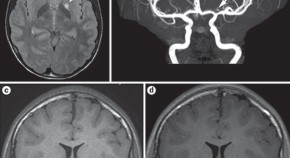

• Inflammatory brain disease can affect patients of all ages, and are becoming increasingly recognized. Central nervous system (CNS) vasculitis is one such disease. Here, the authors describe the current knowledge on this devastating inflammatory brain disease and provide a direct comparison of CNS vasculitis in adults and children. Clinical features, diagnosis, treatment, mimics and the spectrum of the disease are also discussed.

• Marinka Twilt

• Susanne M. Benseler

Review Article